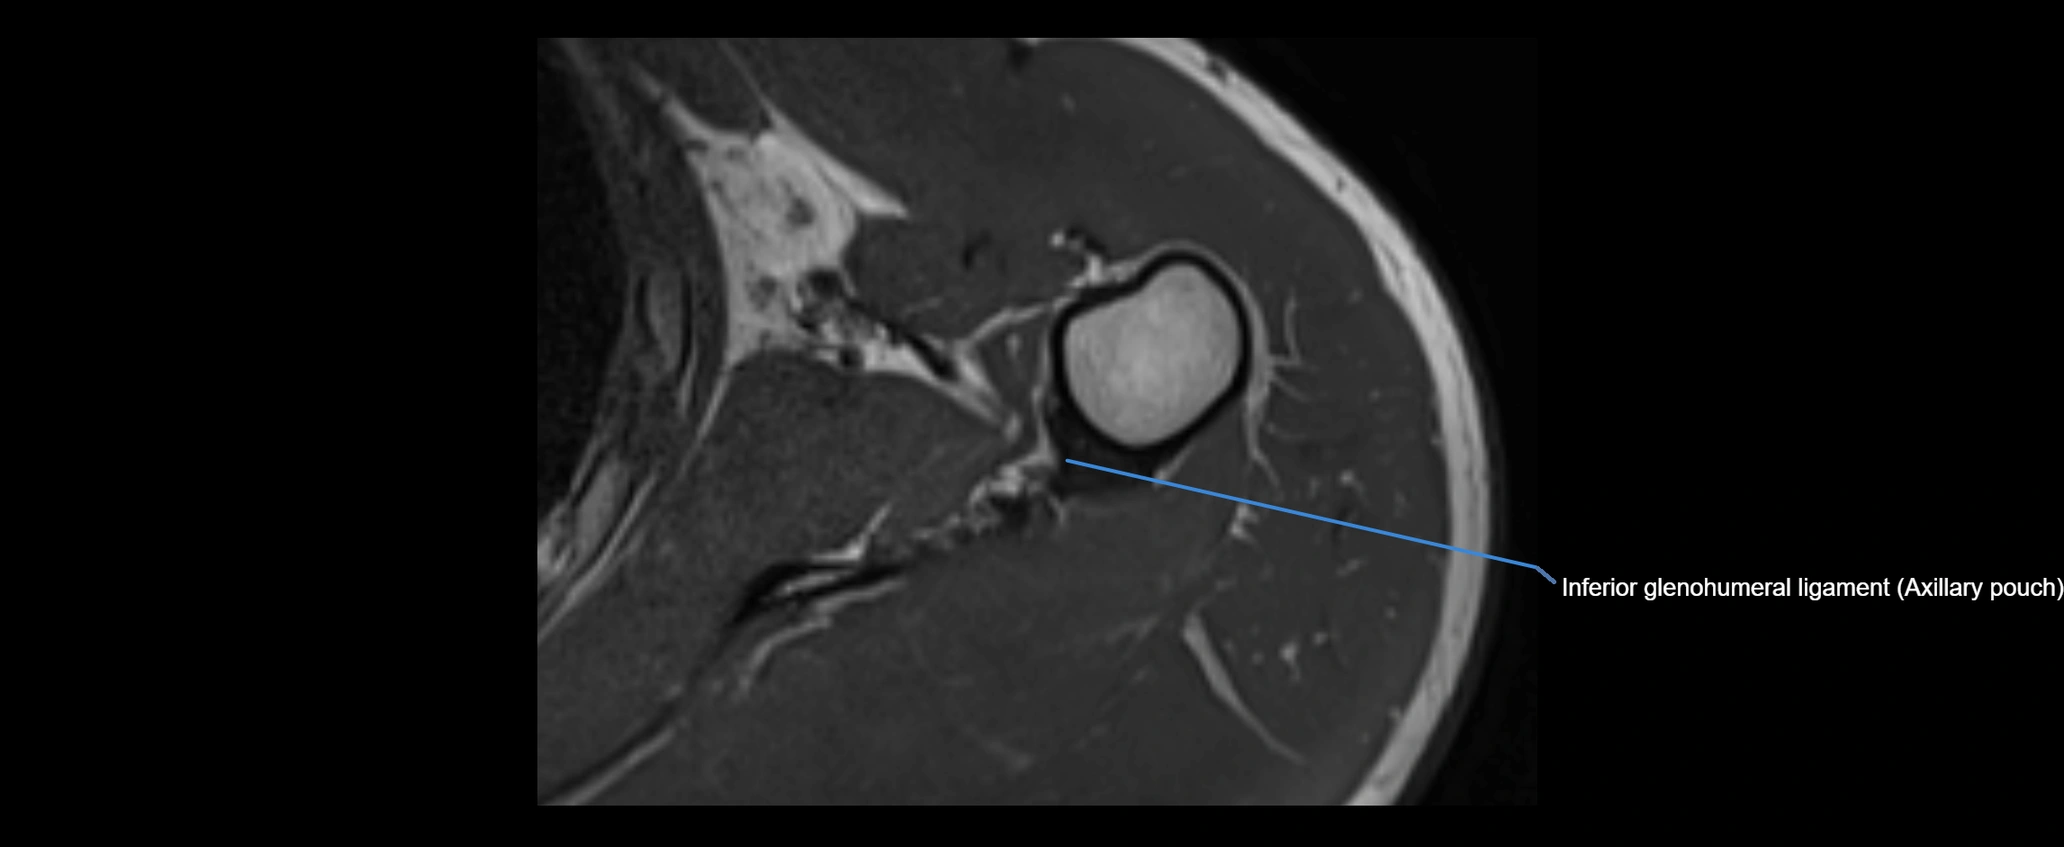

MRI images

image